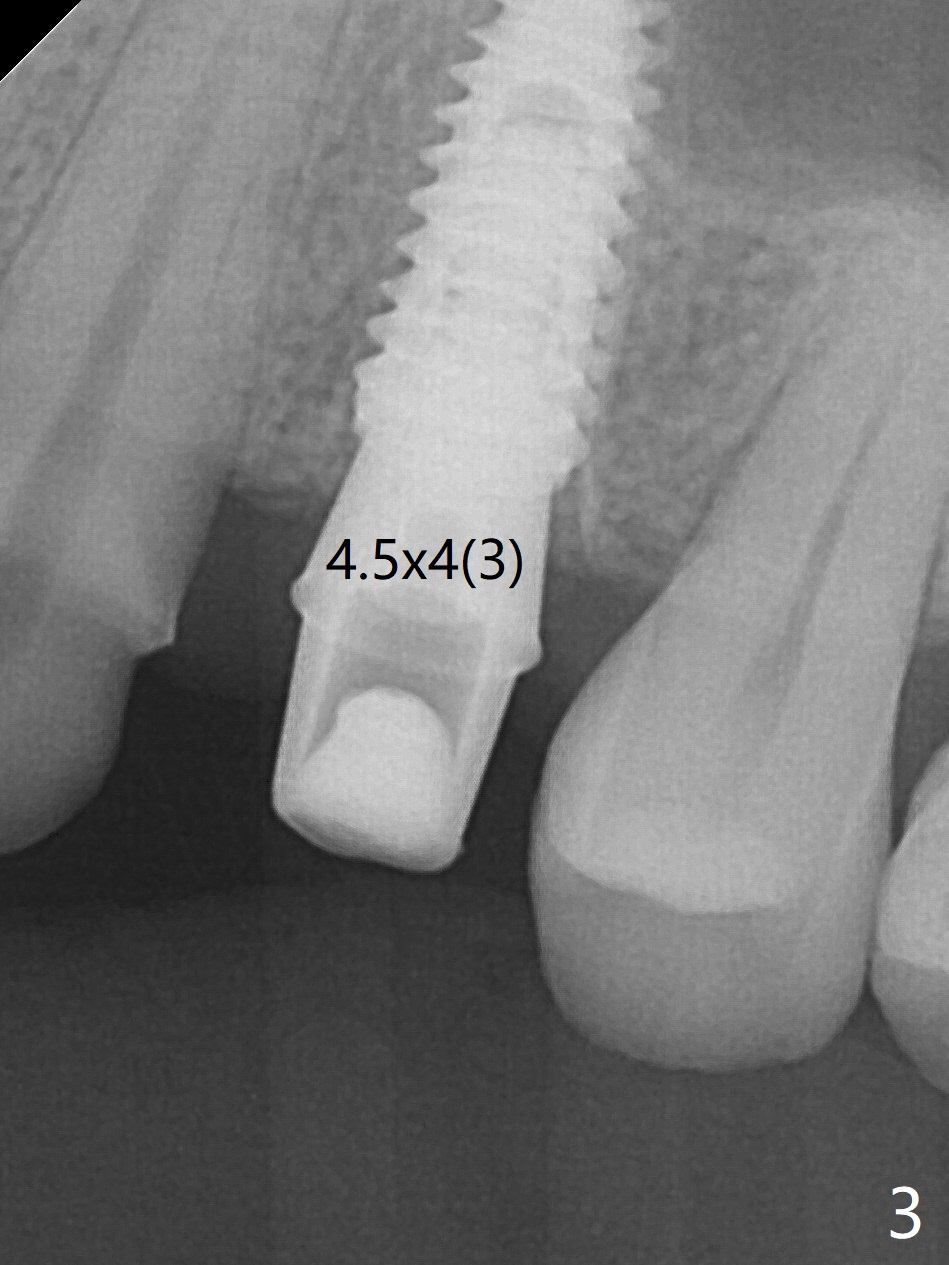

After extraction of the residual roots at #12 and crown prep at #11, osteotomy at #12 is established with Pointed Lindamann bur and 2.2 mm bur for ~ 15 mm. There feels to be sinus floor perforation; a parallel pin is inserted deeper than expected (Fig.1), but there is no membrane perforation. Following sequential osteotomy, a 4x10 mm dummy implant is placed partially with stability (Fig.2). When the same sized definitive implant is placed subcrestally (Fig.3-5 (*: Vera Graft)), the stability remains (~60 Ncm) in spite of the fact that the trajectory is changed once. The coronal socket does not seem to heal 8.5 months postop, in part due to poor hygiene of splinted provisional (Fig.6).